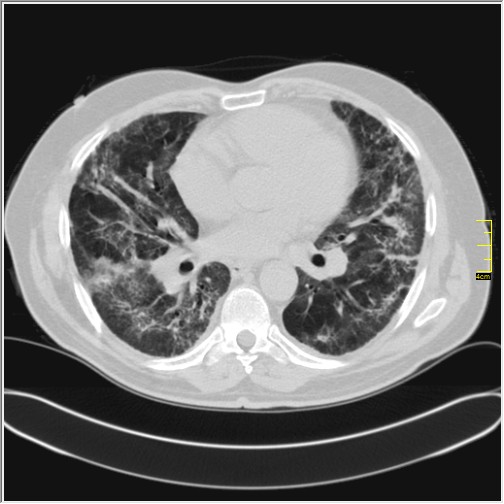

Foto: Aleksandar Ivković Foto: Aleksandar Ivković Foto: Aleksandar Ivković Strašna razlika kod pluća pušača i kovid pozitivne osobe autor: Božica Luković Zdravlje 23. jan. 2021. 12:06 > 23. jan. 2021. 12:15 0 Podeli vest: Radiolog Aleksandar Ivković od početka pandemije daje korisne informacije o svim aspektima kovida 19. On je nedavno uporedio rendgen snimke pluća zdrave osobe, pušača, osobe koja je zaražena gripom H1N1, a onda i osobe koja ima kovid 19. Razlike su zapanjujuće. Podeli vest: Oglas Objavu doktora Ivkovića sa njegovog bloga "Ljudi i ostale laži" prenosimo u celosti."Nedavno sam video u medijima da je neko preneo rdg sliku i razlike kod nalaza zdrave osobe, pušača i bolesnog od kovida 19. Kako nisam baš previše zadovoljan onim što je prikazano, evo kako to izgleda u našoj varijanti. Zdrava osoba CT nalaz kod zdrave osobe podrazumeva da ne postoje nikakvi poremećaji strukture plućnog parenhima, da su krvni sudovi uredni i da nema suženja disajnih puteva, kao i da nema uvećanih limfnih žlezda u hilusima pluća i medijastinumu. Foto: Aleksandar Ivković | Foto: Aleksandar Ivković * Foto: Aleksandar Ivković | Foto: Aleksandar Ivković Zdrava muška osoba mesec dana nakon zapaljenja pluća tokom kovida 19. Nalaz bez nekih posebnih problema iako se naziru tragovi zapaljenja. Snimak u boji je zdrava osoba, nepušač, bez ikakvih bolesti pluća u istoriji. Grip H1N1 Pokazaću samo drastične nalaze kod gripa H1N1, to je znači onaj grip koji je izazvao epidemiju španske groznice i epidemiju 2009. godine koja još uvek nije prestala (svake godine imamo makar 15%). Foto: Aleksandar Ivković | Foto: Aleksandar Ivković * Foto: Aleksandar Ivković | Foto: Aleksandar Ivković * Foto: Aleksandar Ivković | Foto: Aleksandar Ivković * Foto: Aleksandar Ivković | Foto: Aleksandar Ivković Nisu svi pacijenti imali ovakve nalaze, pokazujem one koji su imali tešku kliničku sliku. Kod gripa se sve odvija obično u sedam dana. Kao što se vidi, zapaljenje je bilo jednostrano, uglavnom. Ali kada je dolazilo do pogoršanja, onda je centralno obostrano dolazilo do edema pluća. Pušenje Kod pušača postoje razne varijante nalaza na plućima. U principu nisu tako dramatične kao što su zapaljenja. Nalaz na plućima kod pušača može biti potpuno normalan. Ovo ne pišem zato što podržavam pušenje, naprotiv, veliki sam protivnik, ali iznošenje laži nikada nije dobro. Dve dijagnoze su bitne kao posledica pušenja. Prva je hronična plućna opstruktivna bolest: Foto: Aleksandar Ivković | Foto: Aleksandar Ivković * Foto: Aleksandar Ivković | Foto: Aleksandar Ivković * Foto: Aleksandar Ivković | Foto: Aleksandar Ivković Jasna je razlika u nalazu, posebno na ovim slikama u boji, gde su ta plava polja delovi pluća koji su propali zbog cigareta (može da se uporedi sa zdravim plućima iznad).Druga bolest koja je česta kod pušača je u svakom slučaju karcinom. Foto: Aleksandar Ivković | Foto: Aleksandar Ivković * Foto: Aleksandar Ivković | Foto: Aleksandar Ivković * Foto: Aleksandar Ivković | Foto: Aleksandar Ivković * Foto: Aleksandar Ivković | Foto: Aleksandar Ivković Tkivo koje raste unutar pluća i razjeda ga. Takav je nalaz kod karcinoma pluća. Često je uzrok upotreba cigareta. Kovid 19 O kovidu sam pisao puno puta. Evo nekih slika, radi poređenja. Foto: Aleksandar Ivković | Foto: Aleksandar Ivković * Foto: Aleksandar Ivković | Foto: Aleksandar Ivković * Foto: Aleksandar Ivković | Foto: Aleksandar Ivković * Foto: Aleksandar Ivković | Foto: Aleksandar Ivković Nakon što pacijent bude izlečen od gripa ili kovida 19, pluća se mogu vratiti u normalu.To je razlika u odnosu na posledice upotrebe cigareta. Ovi snimci nisu postavljeni da bi se poredile bolesti, već da bi se ukazalo kako različite bolesti deluju na pluća. I ono što je veoma važno, ako neko dobije jednu od ovih bolesti, ne znači da u toku života neće dobiti drugu.Ne pišem zato smo smatram da sam najpametniji ili najpozvaniji da objašnjavam, nisam kao neki pojedinci ubeđen da samo ja imam znanje i istinu, pišem jer drugi ćute. Pišem jer ima i puno onih koji iznose laži, mora se tome stati na put.A ovi, koji pišu da sam umro, da sam oboleo od karcinoma, ovi koji mi žele da nađem dobro grobno mesto, šta da vam kažem, vi ste mi inspiracija. Svesni ste da sam u pravu i odlično znam da ste već uradili sve da se vakcinišete i mnogi od vas će to uraditi pre mene ali i dalje ćete ubeđivati druge da se ne vakcinišu i da je dobro za njih da se razbole i umru. Ima puno reči za vas u svim našim slovenskim jezicima, znate vi sami šta ste", piše dr Ivković.***Bonus video:https://youtu.be/MWucTT0qBsIPratite nas i na društvenim mrežama:FacebookTwitterInstagram Dr Lukić otkrio spisak svih antibiotika za kovid upalu pluća Zdravlje 0 Dr Žujović: Kako oporaviti pluća posle korone Zdravlje 0 Pet znakova da ti je kovid zahvatio pluća Zdravlje 0 Virusolog Ana Banko ruši veliku zabludu o ruskoj vakcini Emisije 0 aleksandar ivković korona kovid pluća snimak pluća Pratite nas na društvenim mrežama: Koje je tvoje mišljenje o ovoj temi? Učestvuj u diskusiji ili pročitaj komentare Budite prvi koji će ostaviti komentar Pošalji komentar Pročitaj komentare (0)